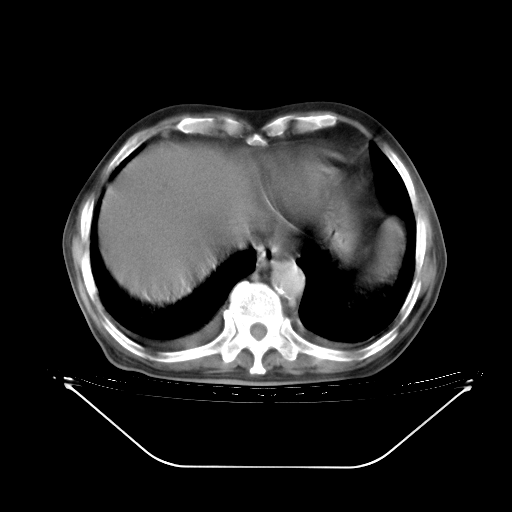

胸腹部CT,诊断意见:左上肺叶钙化灶、左侧胸膜局限性增厚并钙化、胆囊炎。描述部分肺组织呈磨玻璃样改变。

今天复查肺部CT,发现双肺广泛磨玻璃样改变。所以我把3月19日和5月9日相隔50天的肺部CT上传。请大家会诊。

2009年3月19日肺部CT片。

2009年3月19日肺部CT

5月9日肺部CT(在4月27日齐鲁医院肺部CT描述部分肺组织磨玻璃样改变,12天后肺组织广泛磨玻璃样改变)